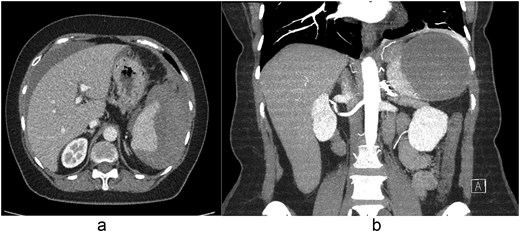

On presentation, she was tachycardic (HR 110 bpm) with stable blood pressure. Laboratory results showed hemoglobin of 11.8 g/dl and WBC of 11.4 × 109/L. Contrast-enhanced computed tomography (CT) of the abdomen demonstrated a large peri-splenic hematoma measuring 8.6 × 10.2 cm with hemoperitoneum (Fig. 1a and b). Chest X-ray and electrocardiogram were unremarkable. She was transferred to a higher-level facility, during which she developed hypotension (BP 80/40 mmHg) that responded to IV fluids.

(a) Axial and (b) coronal contrast-enhanced CT images demonstrating a peri-splenic hematoma measuring 8.6 × 10.2 cm with associated hemoperitoneum.